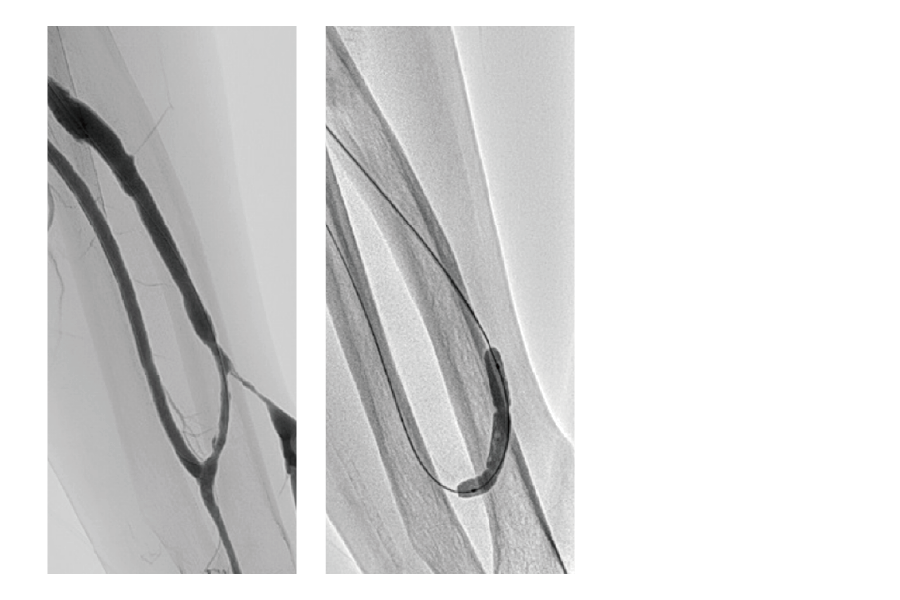

BEFORE

AFTER

別疾患で入院中だった患者様が急性下肢閉塞を起こしましたが、

速やかな治療で改善し、2 日後に退院しました。